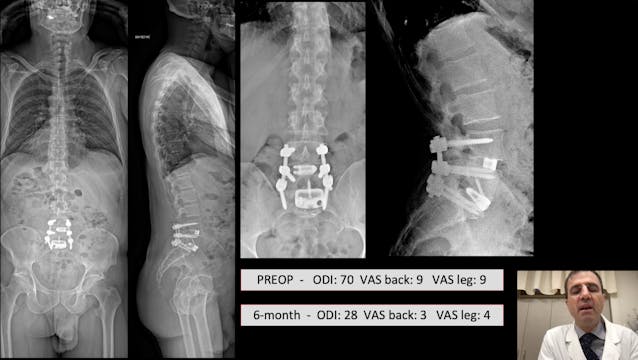

Adult spine deformity - Where we stand and the road ahead

Adult spine deformity